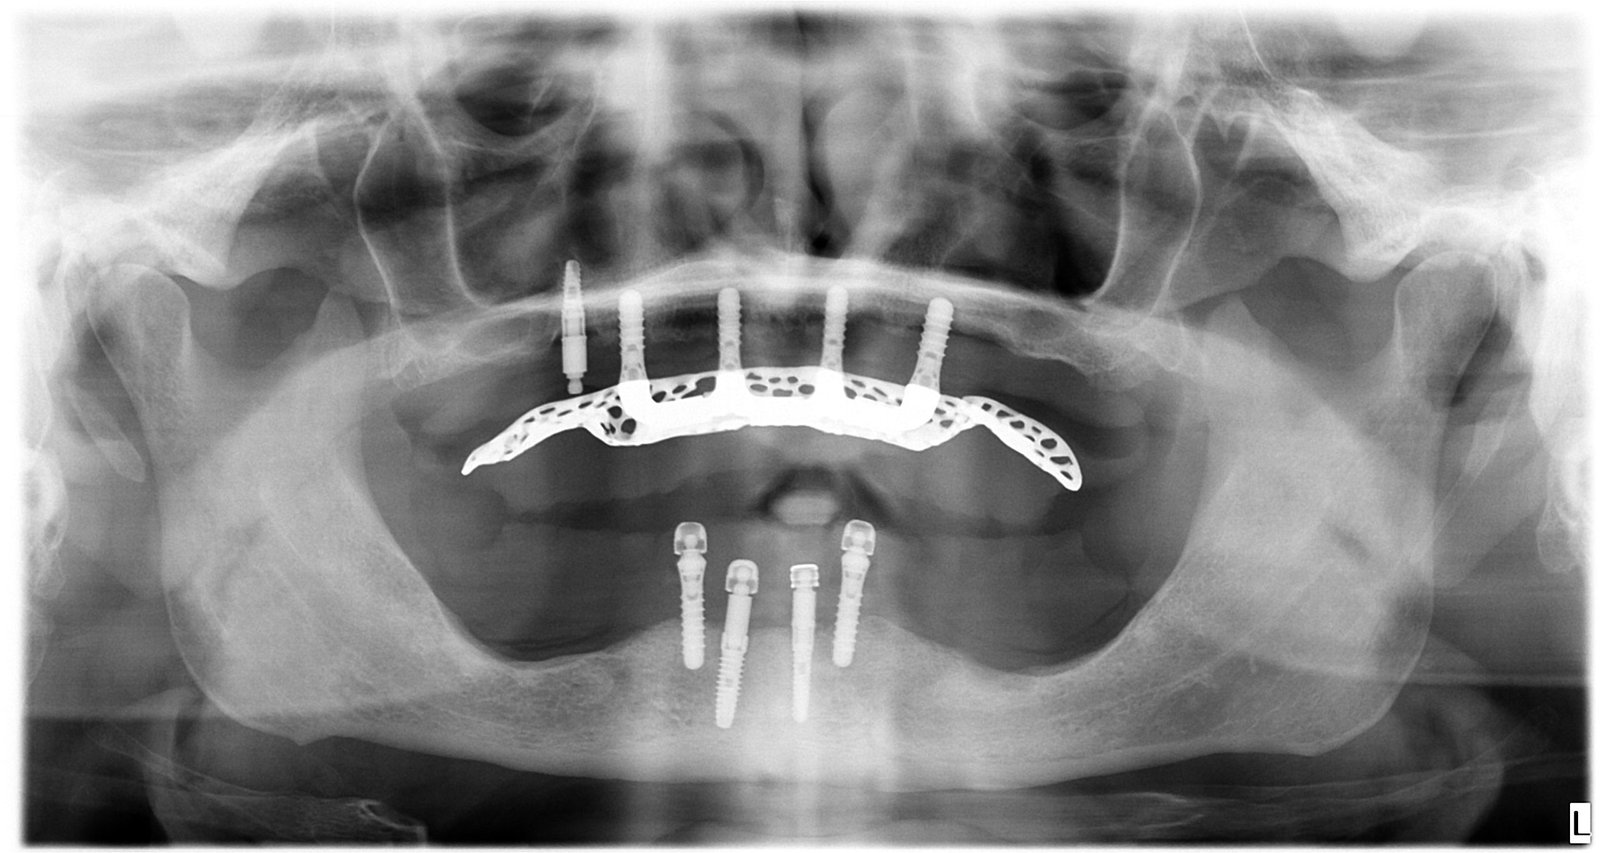

Caso 1 - caso de Carga inmediata

La paciente acudió con la necesidad de recuperar sus dientes de forma rápida y sin largos tiempos de espera. Gracias a la técnica de carga inmediata, colocamos dientes fijos el mismo día, devolviéndole su sonrisa de manera inmediata y segura.

Esta imagen muestra la planificación precisa del tratamiento de carga inmediata, clave para garantizar estabilidad desde el primer momento.